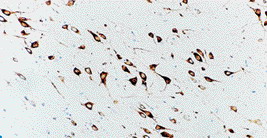

生长相关磷蛋白43(GAP43)是神经生长锥体的主要蛋白和某些终末突触前体。为轴突生长和突触形成中的后备蛋白。据报道在几种神经系统中,GAP43高表达在神经元扩展到轴突,表达在成人神经元完好轴突损伤的发育或再生中。GAP43最显著的特性为生长相关蛋白,尽管在体外GAP43的正常活动还不清楚。GAP43能够与钙结合抑制磷酸肌醇磷酸激酶,通过蛋白激酶C磷酸化,影响神经递质释放和增强非神经细胞伪足的伸延。

人大脑,正常成人大脑皮质:免疫组化染色生长相关磷蛋白43(GAP43)采用NCL–GAP43。图示神经元与树突顶端强染色。石蜡切片。